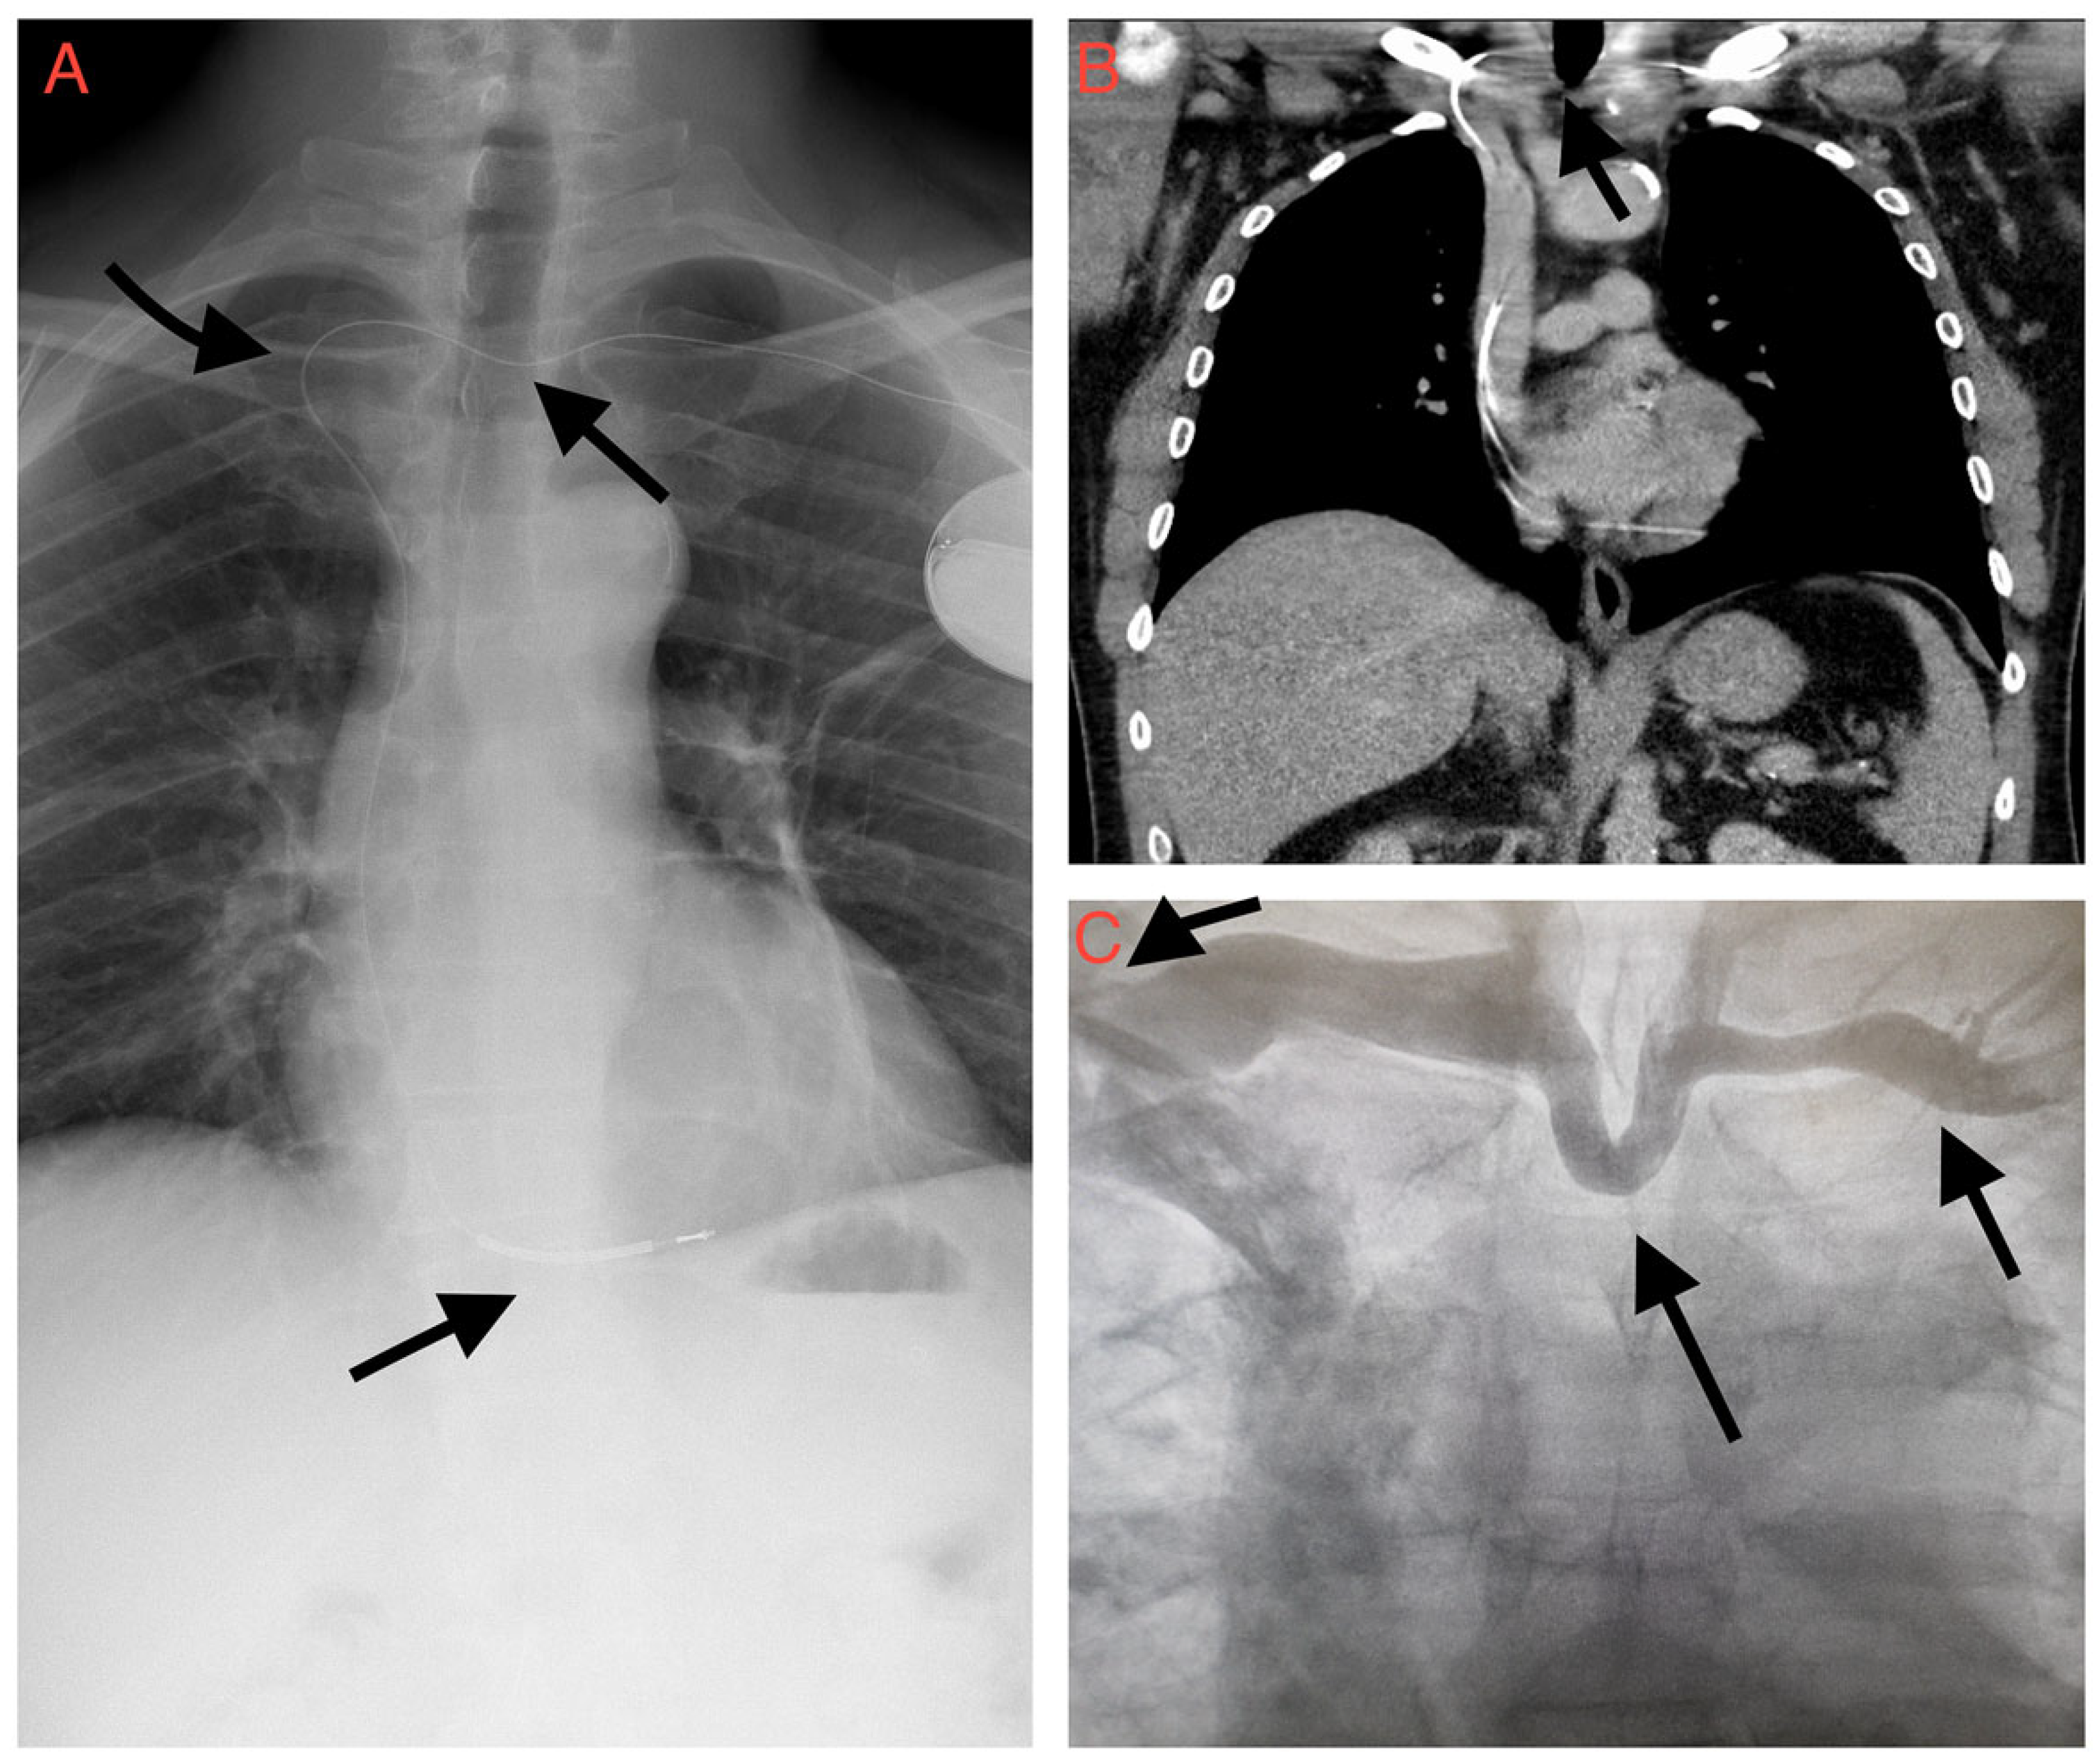

ICD Insertion in Previously Undiagnosed Left Brachiocephalic Vein Obstruction